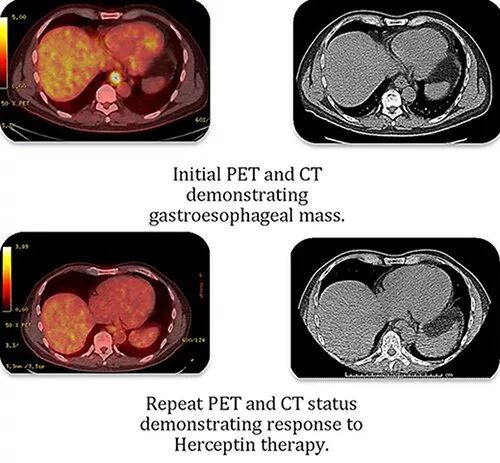

61岁的陈先生在2015年5月因胃酸倒流胃镜检查发现肿块,活检确诊为胃食管腺癌(图2-上),已出现肺转移,基因检测发现HER2过度表达。接受联合化疗:包括多西紫杉、顺铂、卡培他滨和曲妥珠单抗(赫赛汀)。2015年8月,PET CT显示结节部位完全消失。2016年2月,检查未发现进展,停止治疗,继续曲妥珠单抗治疗(每3周6mg/kg)。耐受性良好,心脏状态良好。然而,3个月的曲妥珠单抗治疗后,PET CT显示左上经上淋巴结有进展。曲妥珠单抗治疗联合紫杉醇继续治疗。2个月后,轻微病情发展,改FOLFIRI(伊立替康+亚叶酸钙+5氟尿嘧啶)和曲妥珠单抗治疗。6个疗程后完全缓解。进行放疗辅助,并继续进行曲妥珠单抗治疗。2017年6月PET CT检查无复发、无转移(图2-下)。自诊断转移性腺癌后30个月使用曲妥珠单抗维持治疗反应一直很好。